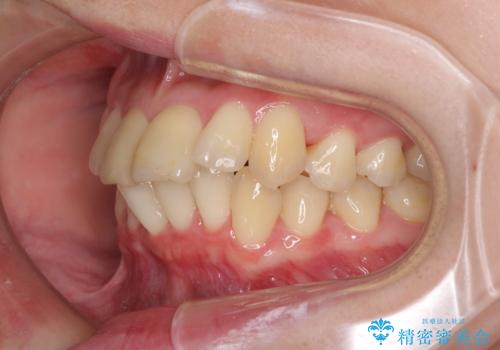

上下前歯のデコボコをきれいに インビザラインによる矯正治療

- 前歯の著しい叢生と前突感を気にして来院された患者様です。

叢生が強いため、事前に前歯をワイヤー矯正で速やかに叢生を解消し、その後はインビザラインにて矯正治療を行うこととしました。

ワイヤー矯正を併用したことで前歯の叢生を速やかに解消することができました。

一方口元の突出感を改善するために時間がかかり、2年超を要しましたが、満足のいく仕上がりとなりました。